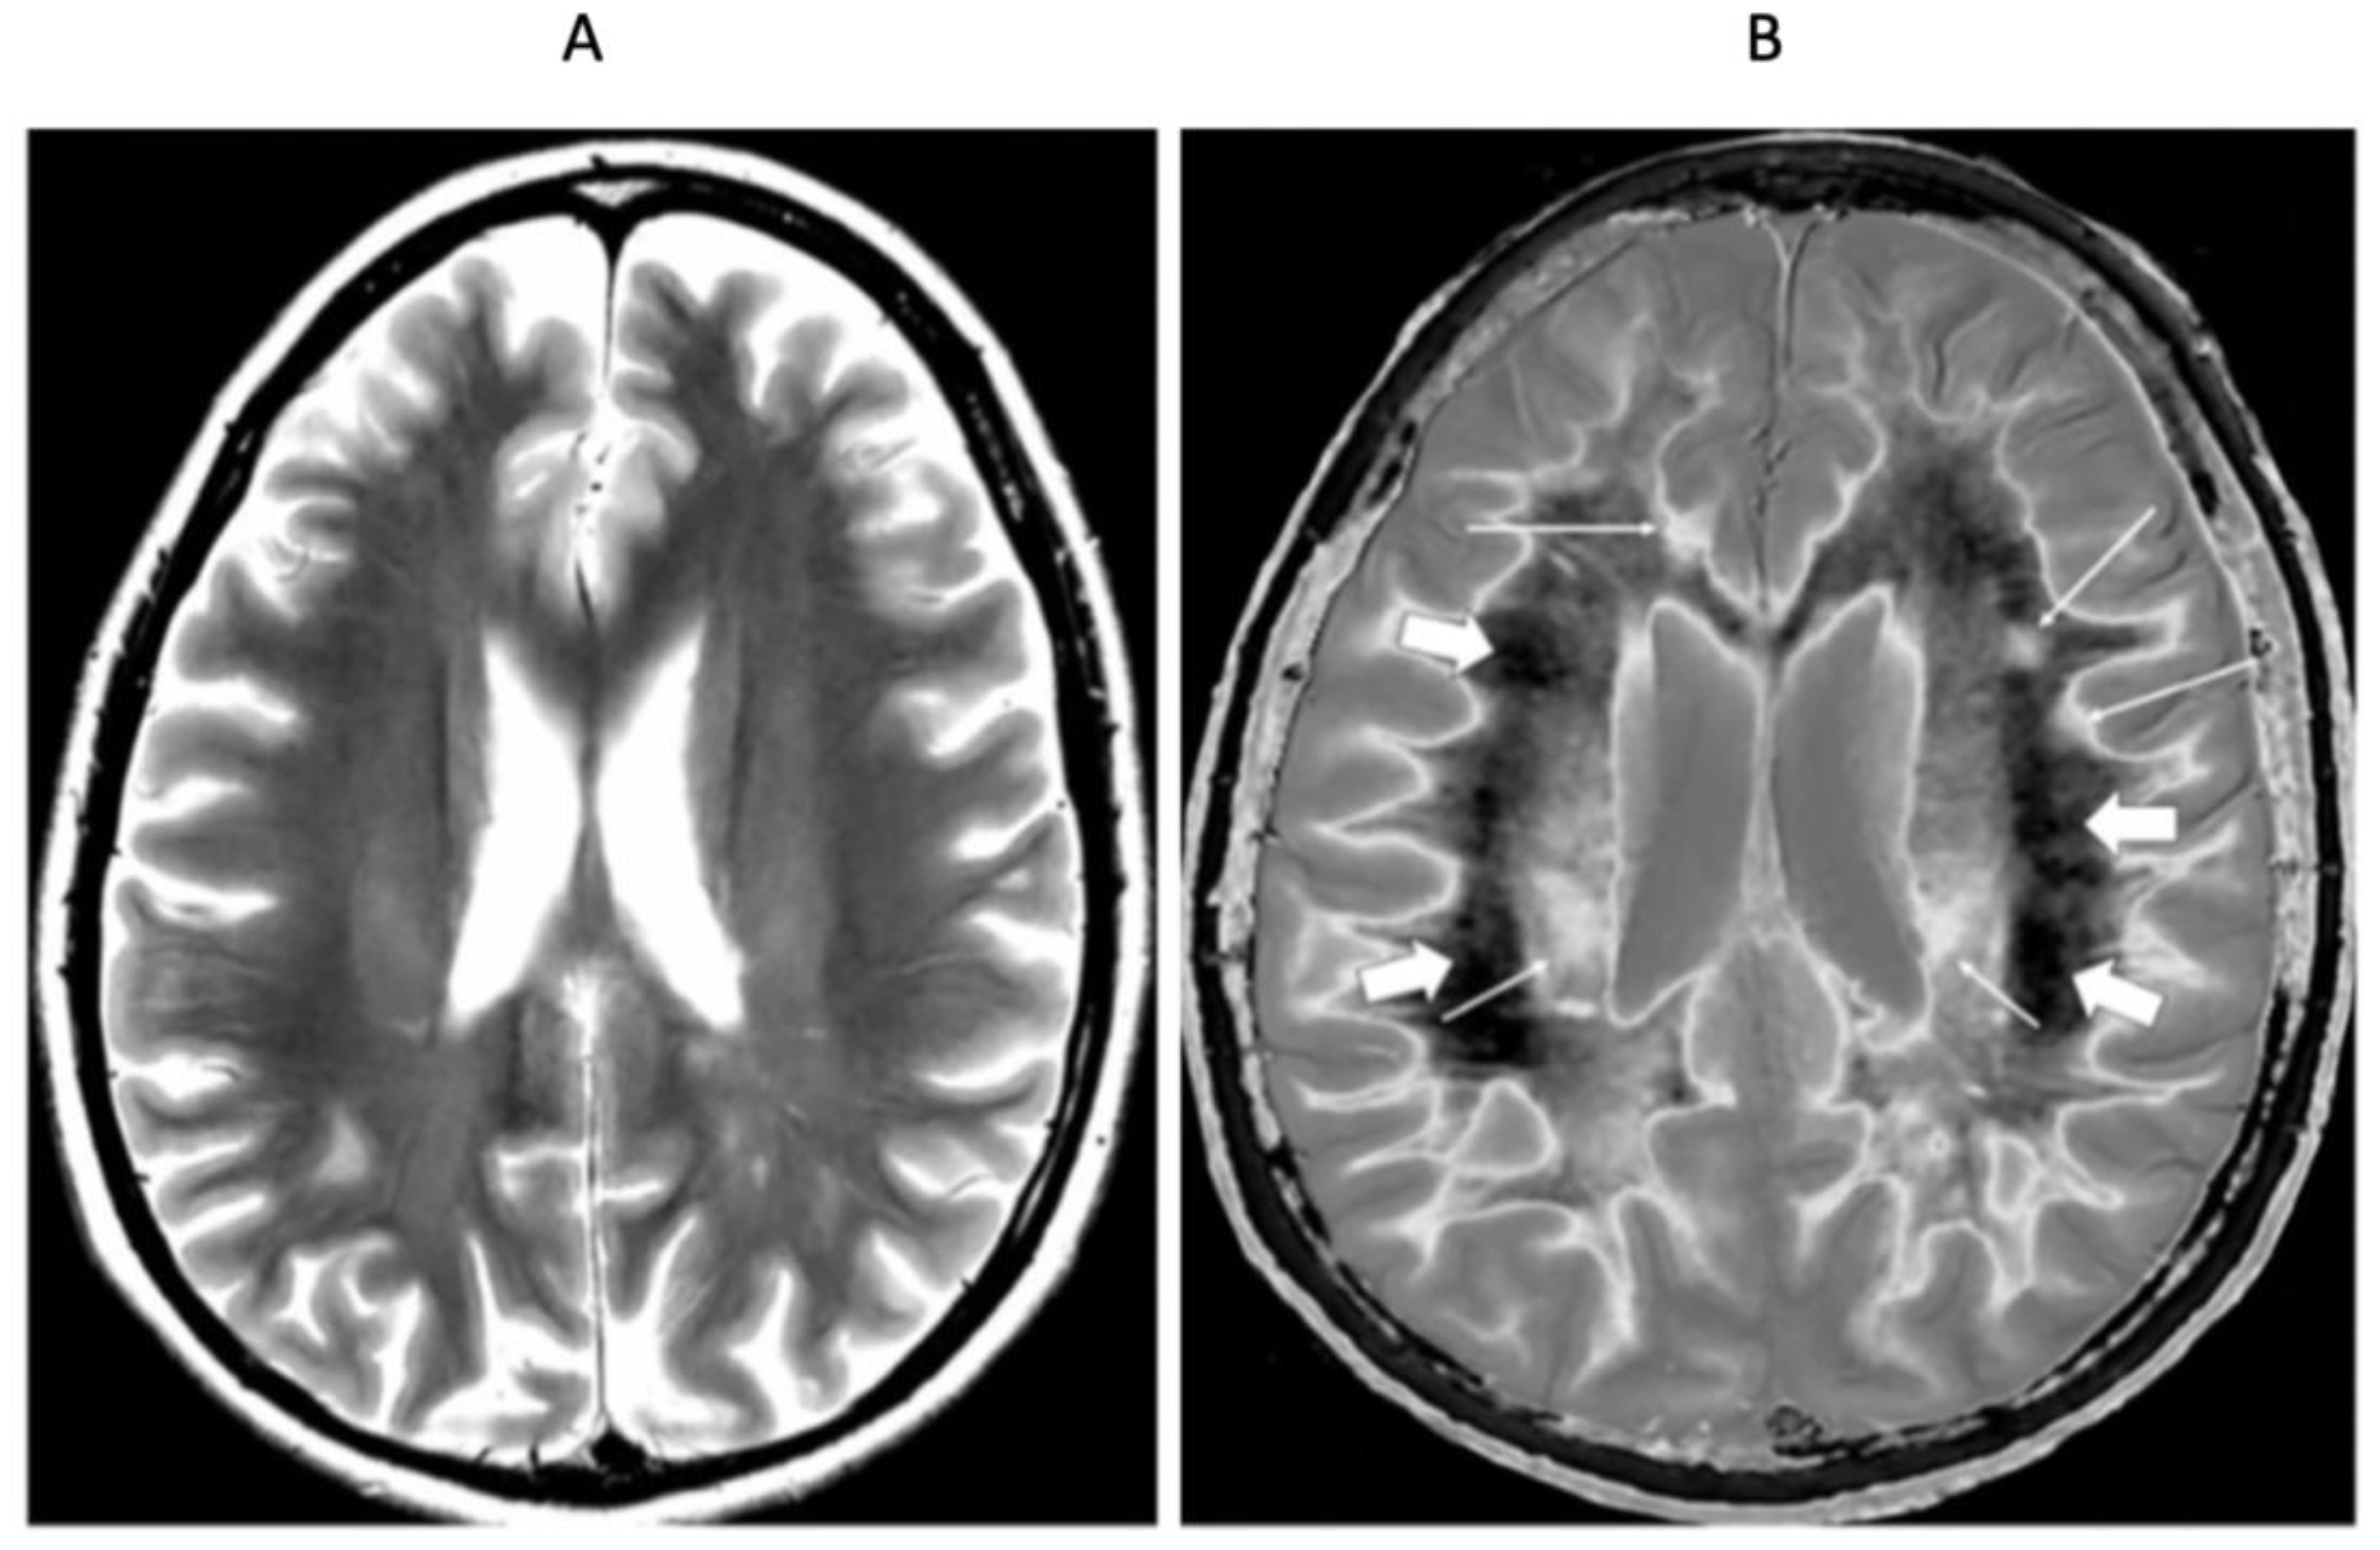

4. Illustrative Cases

5.2.1. Whiteout Sign

5.2.2. Grayout Signs